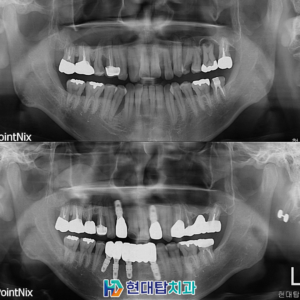

위 환자분은 52년생의 여성분으로

타원에서 진행하신 임플란트와 틀니를

사용 중이셨는데 틀니를 지지해 주던

치아가 파절되어 내원해 주셨습니다.

기존의 틀니를 사용하실 때부터

불편함이 많이 있으셨다고 하셔서

양쪽 위 8개의 임플란트를 식립하여

11개의 치아를 연결하는 브릿지의 형식으로

진행하기로 하셨고, 상태가 좋지 않던 오른쪽 아래

작은 어금니들은 신경치료 후 보철을 진행하였습니다.

또한 기존의 타원 임플란트 들의 보철물을

식립 예정인 임플란트와 교합이 잘 맞을 수 있도록

교체하도록 설명드렸고 치료 계획 수립하였습니다.

술후 파노라마입니다.

치아의 갯수가 많이 없다 보니

전체적으로 치아의 씹는 균형이 많이 무너진 상태여서

차근차근 맞춰가며 최종 보철까지 문제없이 합착하였습니다.

또한 예후가 불량했던 오른쪽 아래

작은 어금니들도 신경관 내부를 단단한 재료로

메워 신경치료를 진행한 후 보철까지 완료하었습니다.